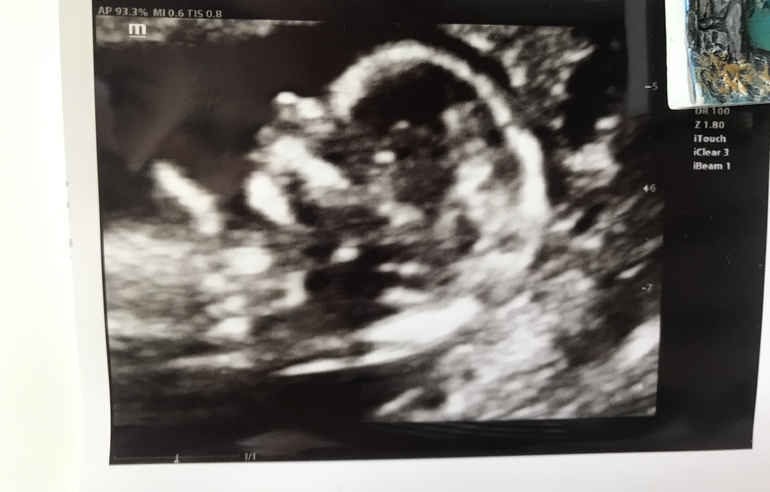

Вчера ходила на первый скрининг😊 все показатели в норме. Малыш очень активный. Доктор назвал его «танцор»😃

Даже пол определили - мальчик 👶🏻

Но все же доля сомнения есть, что может все таки девочка 👧🏻☺️

Знакомьтесь 😁